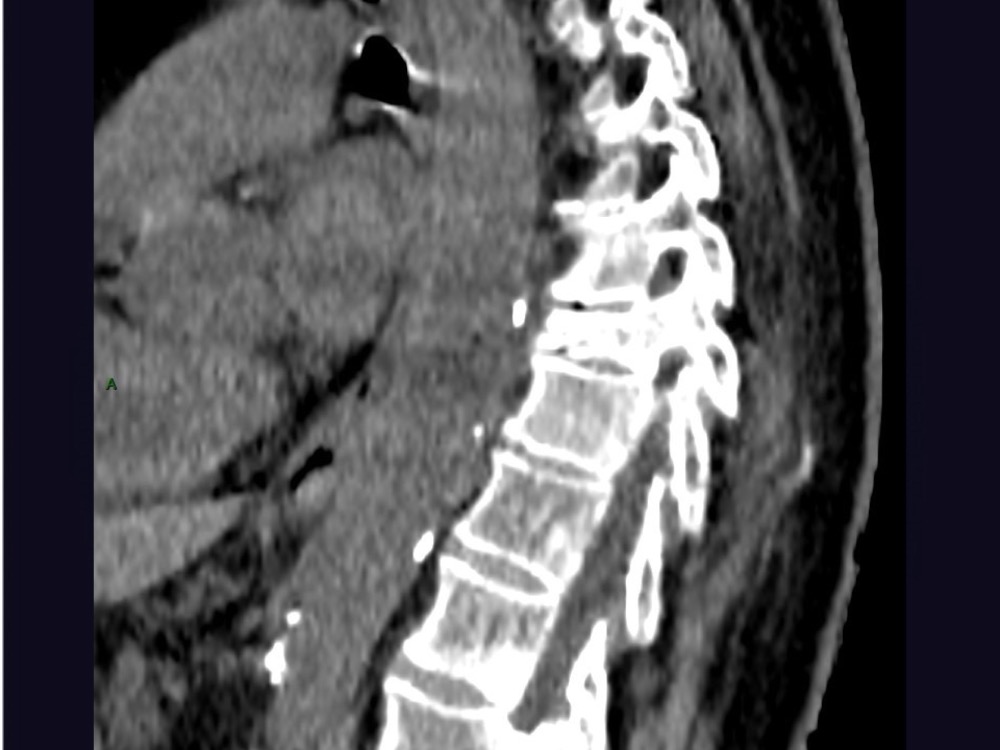

Aboudaram / Thiry 22/06/2020